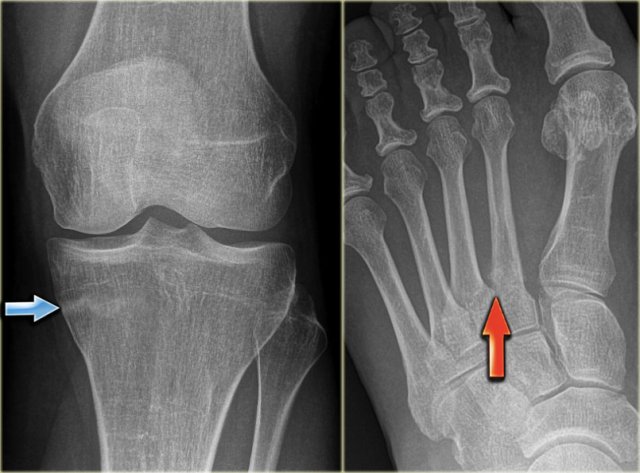

Here the reactive sclerosis is the most obvious finding on the X-ray.

There is reactive sclerosis with a nidus that is barely visible on the radiograph (blue arrow), but clearly visible on the CT (red arrows).

CT scan is usually very helpful in detecting the nidus and differentiating osteoid osteoma from other sclerotic lesions like osteoblastoma, osteomyelitis, arthritis, stress fracture and enostosis.